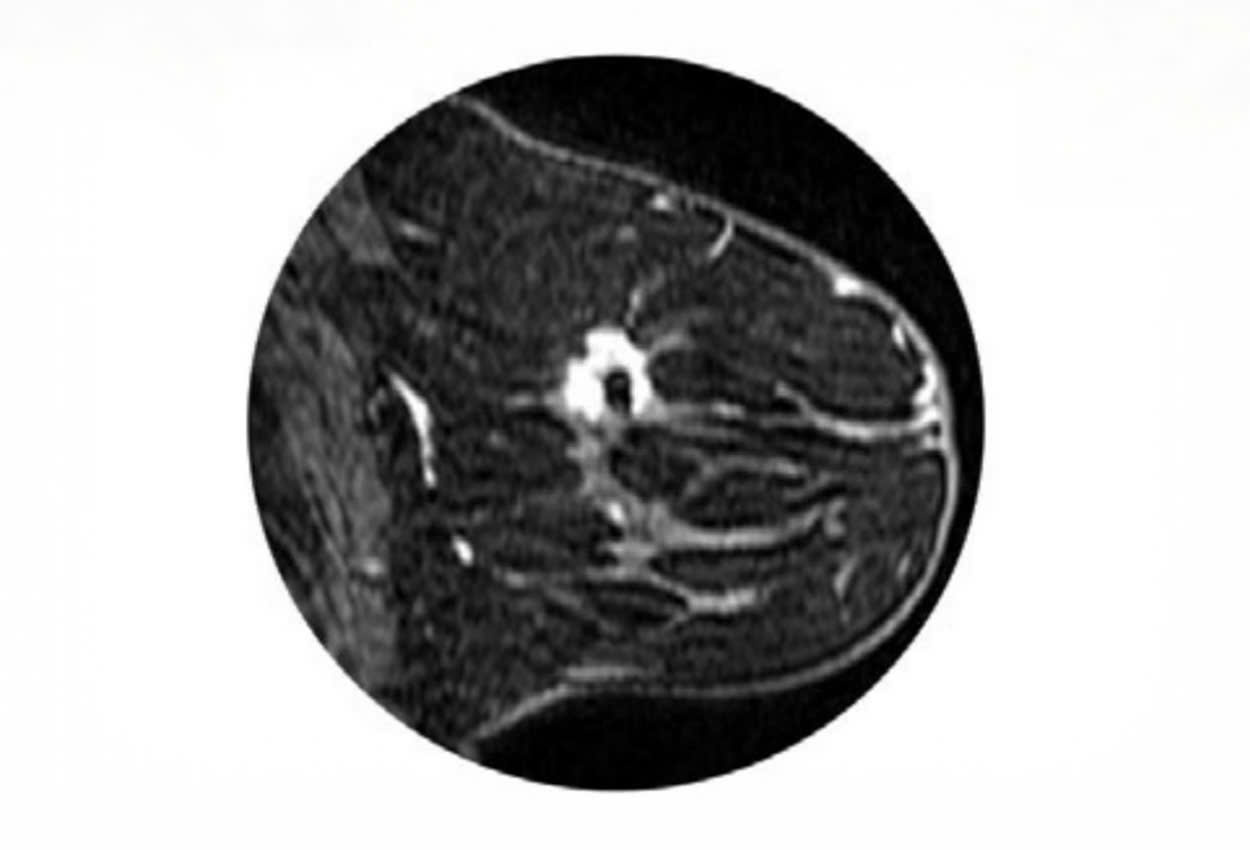

Thiết bị định vị mô vú SenoMark UltraCor dùng để đánh dấu mô vú bằng X-quang và siêu âm trong quy trình sinh thiết vú qua da.

- Hiển thị hình ảnh dưới siêu âm vĩnh viễn

- 4 Hình dạng khác biệt có mức độ hiển thị khác nhau dưới MRI